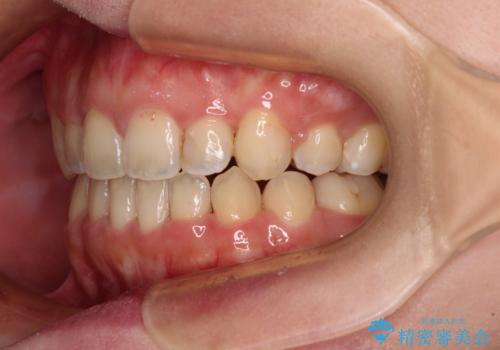

八重歯とは別に上下前歯の隙間という問題もありました。こちらは舌突出癖によるものと考えられたため、舌のトレーニングをしっかりと行っていただきました。